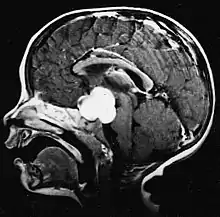

meduloblastomas O meduloblastoma é o tumor cerebral maligno mais comum em crianças. A maior incidência ocorre em crianças entre as idades de 2 e 7 anos. O maior risco de doença permanece na infância, pois o meduloblastoma é muito raro em pessoas com mais de 21 anos.

Este tumor é típico da fossa posterior, onde se localiza em ambos os hemisférios do cerebelo ou no vermis cerebelar. Por ser invasivo e de crescimento rápido, geralmente se espalha para outras partes do sistema nervoso central (SNC) através do LCR e pode se infiltrar no assoalho do quarto ventrículo próximo e nas meninges. Mais raramente, podem ocorrer metástases adicionais no SNC. Quando a malignidade ocorre, os sintomas incluem perda de equilíbrio, incoordenação, diplopia, disartria e devido ao envolvimento do quarto ventrículo, que muitas vezes resulta em hidrocefalia obstrutiva, cefaleia, náuseas e vômitos e marcha instável.

A ressonância magnética geralmente mostra uma lesão maciça com realce de contraste envolvendo o cerebelo. Como mencionado acima, o meduloblastoma tem alta propensão a infiltrar localmente as leptomeninges, bem como a se espalhar pelo espaço subaracnóideo, envolvendo os ventrículos, a convexidade cerebral e as superfícies leptomeníngeas da coluna. Consequentemente, é necessário trazer todo o eixo cranioespinhal em ressonância.

O objetivo da cirurgia é remover o máximo possível da massa apresentada pela lesão. De fato, os tumores residuais pós-operatórios resultam em pior prognóstico. Também um prenúncio de um prognóstico desfavorável é a presença de células tumorais no líquido cefalorraquidiano ou a detecção por ressonância de metástases leptomeníngeas. A cirurgia por si só geralmente não é curativa. Em alguns casos, no entanto, pode ocorrer irradiação terapêutica do eixo cranioespinhal, focada no local do tumor primário. A adição de quimioterapia após a radioterapia aumenta a taxa de cura. Medicamentos à base de platina (cisplatina ou carboplatina), etoposídeo e um agente alquilante (ciclofosfamida ou lomustina) são usados com vincristina. Com tratamento adequado, casos de longa sobrevida de mais de 3 anos em pacientes com meduloblastoma variam de 60 a 60 anos e 80 Por cento.